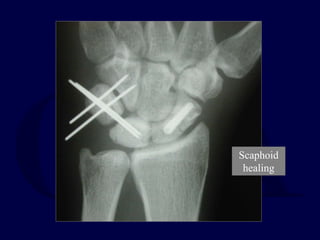

Scaphoid

healing